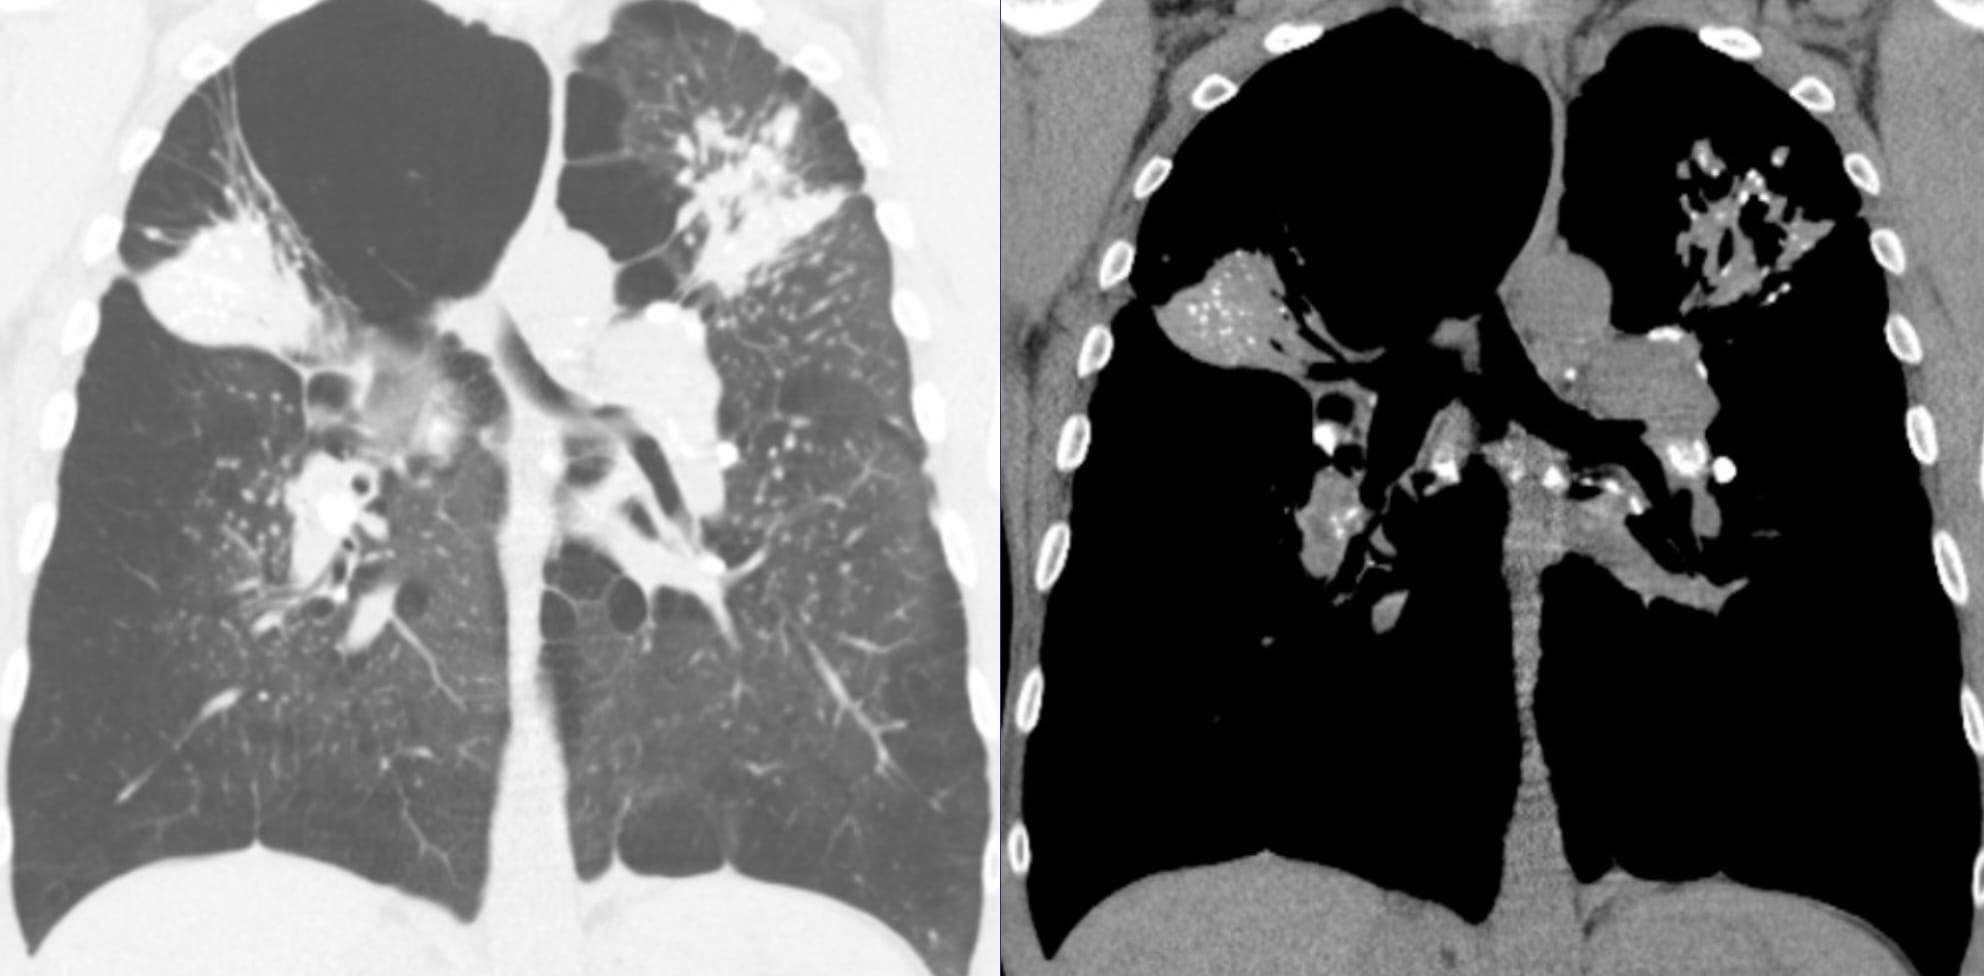

- Sarcoidosis and Fibrosing Pneumoconioses